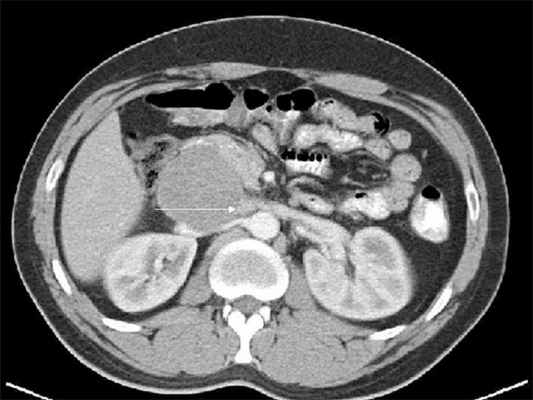

Ультразвуковая эхография помогает определить размеры и глубину расположения опухоли, выяснить ее связь с сосудами; компьютерная томография позволяет определить опухоли диаметром начиная с 1,5-2,0 см, точное их распространение, топографию, обнаружить увеличение лимфатических узлов.

В случае забрюшинних неорганных опухолях обязательно выполняют биопсию для цитологического и гистологического исследований. Чрезкожную аспирационную пункционную биопсию осуществляют в случае расположения забрюшинной опухоли на боковых стенках таза. В случае тазового расположения опухоли применяют пункционную биопсию через заднюю стенку влагалища или путем прокола ишиоректального участка. Помогают проводить прицельную биопсию эхография и компьютерная томография.

Пункционная биопсия позволяет уточнить характер процесса и определить морфологическое строение новообразования. Чаще пункционная биопсия является завершающим этапом обследования больного после уточнения локализации, размеров и взаимоотношения опухоли с соседними органами.